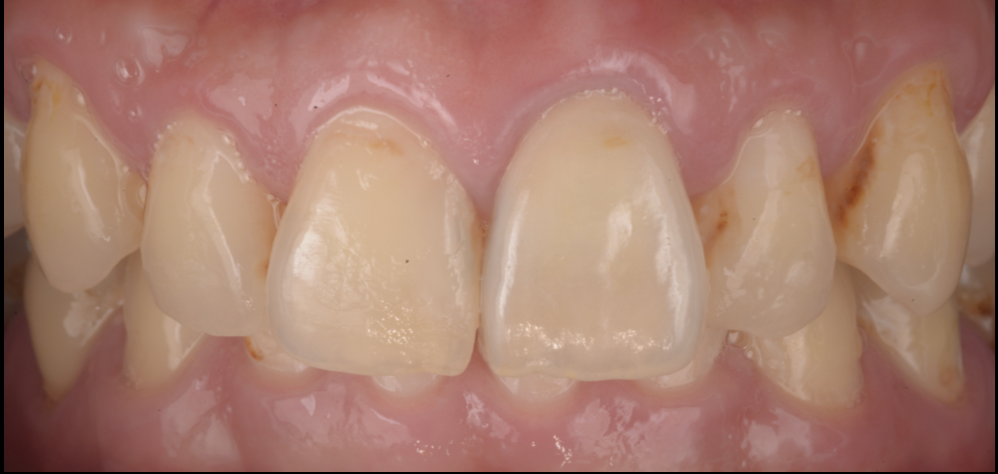

虫歯と歯周病で崩れた前歯・奥歯を、セラミック+リッジオーギュメンテーション+咬合再構成で回復した症例(池袋)

- 担当医

- 生野誠

- 主訴

- 虫歯と歯周病で歯がボロボロ。見た目と噛みにくさが気になる。

- 期間

- 1年

- 費用

- 160万

- 治療内容

- 1)歯周・虫歯のコントロール

補綴治療の前に、歯ぐきの炎症や感染源(虫歯・不良補綴など)を整理し、治療の土台を作りました。

2)右上3欠損:リッジオーギュメンテーション+ブリッジ

欠損部は、ブリッジによる回復を計画。審美性と清掃性、そして補綴の形態を整えるために、リッジオーギュメンテーション(顎堤増大)で歯ぐき・土台のボリュームを整えた上で、ブリッジで回復しました。

3)その他:クラウン/ベニアで審美と形態を回復

虫歯・歯質の状態に応じて、セラミックのクラウン・ベニアを使い分け、歯の形と色調、左右差を整えました。

4)咬合再構成(全体の噛み合わせを整える)

「1本ずつ綺麗にする」だけでは、噛み合わせの偏りや過大な負担が残ることがあります。

本症例では全体のバランスを見ながら咬合再構成を行い、見た目と機能の両立、長期安定を目指しました。

- 治療に伴うリスク

- • セラミック治療は、噛み合わせや歯ぎしりの影響を受けます。必要に応じてナイトガード等の併用が望ましい場合があります。

• 歯周病は再燃リスクがあるため、メンテナンス(定期管理)が治療結果の安定に重要です。

• リッジオーギュメンテーションは外科処置のため、腫れ・痛み・治癒期間などの説明が必要です(個人差あり)。